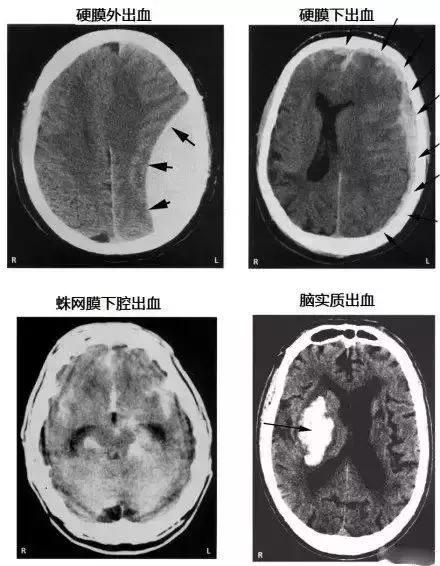

各种颅内出血

几种类型脑出血的CT表现